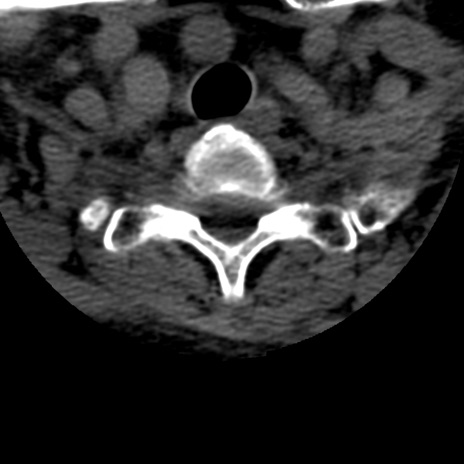

症例50 頚椎CT(横断像)

頚椎CT